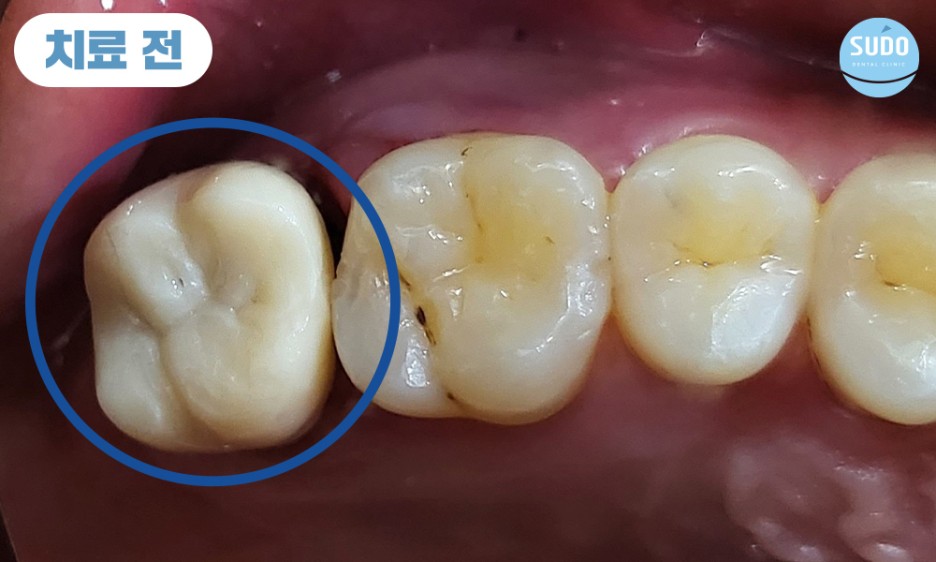

위 환자분은 20대 후반의 남성분으로, 오른쪽 위 가장 안쪽 어금니 보철물이 빠질 것 같다고 하시며 수도치과로 내원해 주셨습니다. 보철물이 완전히 부러진 상태는 아니라서 기존 보철물을 제거한 후 치아 내부 상태를 확인하였습니다.

상태가 양호하다면 부족한 부분을 보강하기 위해 기둥을 세우고 재보철치료를 진행할 수 있었으나, 내부 상태가 좋지 않을 경우 치아를 발치하고 임플란트 치료를 진행해야 할 것으로 설명드렸습니다.